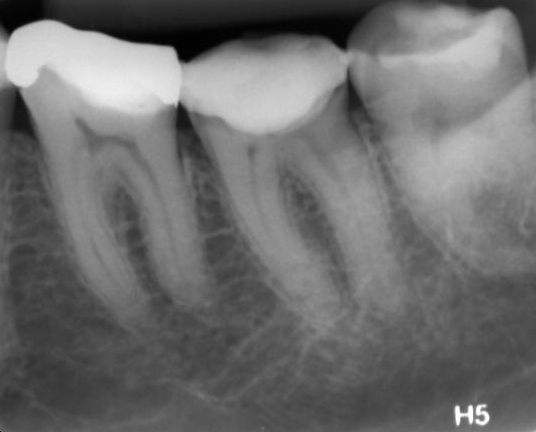

- Figura 8 – Controle radiográfico após 17 meses.

Após 17 meses, a paciente compareceu para consulta de controle. Na radiografia foi possível observar sucesso endodôntico caracterizado por ausência de sinais e sintomas, dente em função fisiológica, normalidade do periápice e reabsorção do surplus de MTA Fillapex.